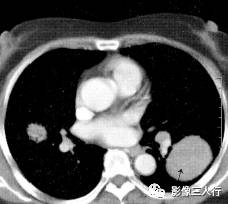

胸部CT图像显示,在含气少的致密肺的背景上见到含气的支气管,表现为两种形态: ①在大片肺实变病灶内的细条状空气密度影;②直径Imm的小泡状空气密度影,连续的几 个层面都能出现(图2、图3)。该征象表明:①近侧气道通畅;②肺泡内的空气经吸收(肺不张)或取代(肺炎、肺癌),或两者综合而消失。通畅含气的支气管在肺泡实变高 密度区内表现为管腔内低密度充气轮廓。